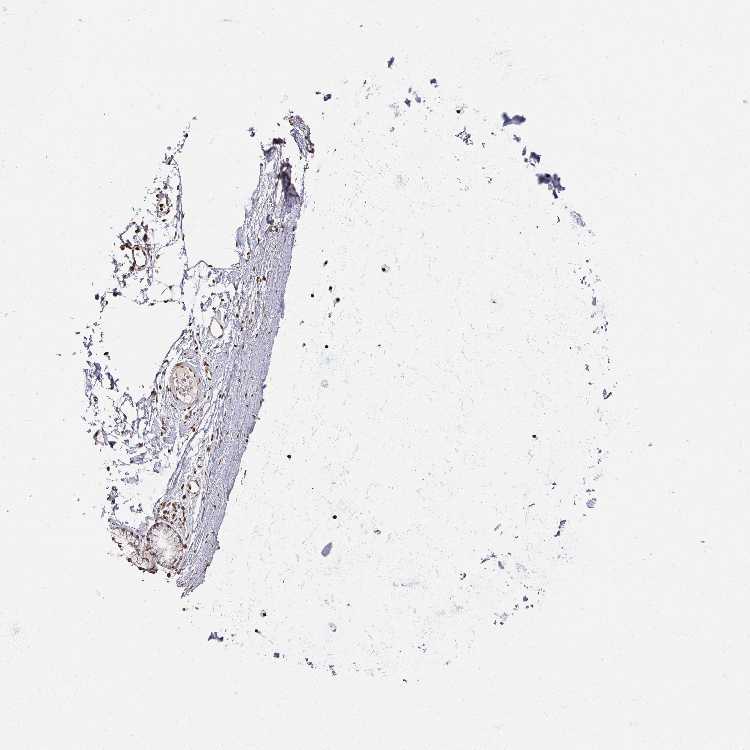

SOFT TISSUE 2 - Antibody stainingi

Antibody staining in the annotated cell types in the current human tissue is reported as not detected, low, medium, or high, based on conventional immunohistochemistry profiling in selected tissues. This score is based on the combination of the staining intensity and fraction of stained cells.

Each image is clickable and will lead to virtual microscopy that enables deeper exploration of all samples and also displays staining intensity scores, fraction scores and subcellular localization as well as patient and tissue information for each sample.

Antibody HPA050863

Fibroblasts Medium

Peripheral nerve Medium